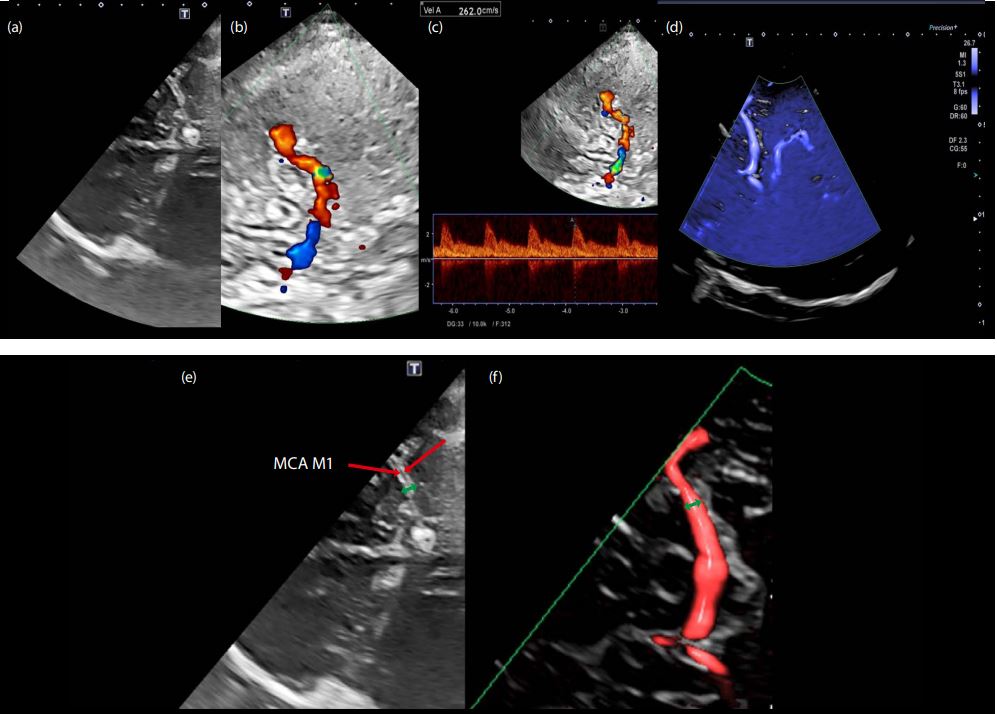

Як ви можете бачити в цьому випадку (Мал. 4), морфологічний діаметр зображення в техніці кольорового та енергетичного доплера не представлений морфологічним дослідженням у B-режимі (Мал. 3). Розвиток досліджень у Bрежимі також дозволив правильно ідентифікувати техніку як ТК ВС.

Малюнок 3

Малюнок 4

Малюнок 5. Внутрішньочерепний стеноз, досліджений за допомогою В-режиму та кольорового доплерівського картування; в середньому дистальному сегменті М1 є фокусна точка з ефектом еляйзінгу (Мал. 5б), де виявлене прискорення 260 см/с. (рис. 5в).

У цьому випадку КДК не дає морфологічної картини, що демонструє стеноз менше 5 мм (Мал. 5а та 5д).

Робочим інструментом може бути ADF для подолання описаних обмежень (Мал. 5d і 5f).